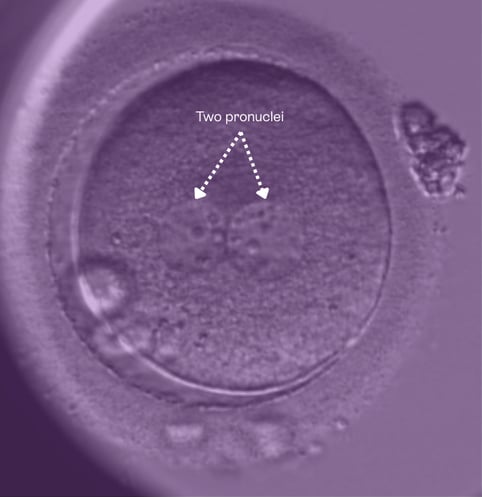

An embryo showing two pronuclei after fertilisation at Care Fertility

After fertilisation, embryos usually show two pronuclei (2PN) — one from the egg and one from the sperm. In the past, embryos that didn’t show this typical pattern were often labelled as abnormal and not taken further.

Embryo with 2PNWe look for two tiny structures called pronuclei. This tells us the egg and sperm have done their bit and fertilisation has taken place.